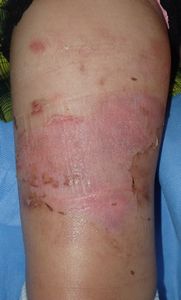

4歳7ヶ月女。埼玉県在住。

2015年10月19日夜,カップめんの容器を倒して右大腿に熱傷。〇〇大学附属病院救急室を受診し,ガーゼと軟膏(名前は不明)で治療。帰宅後,母親がネットで熱傷治療について調べ,翌日当科を受診。

10月20日,当科受診。水疱膜を除去し,プラスモイストで被覆。

| 10月20日 | 10月26日 | 11月2日 |